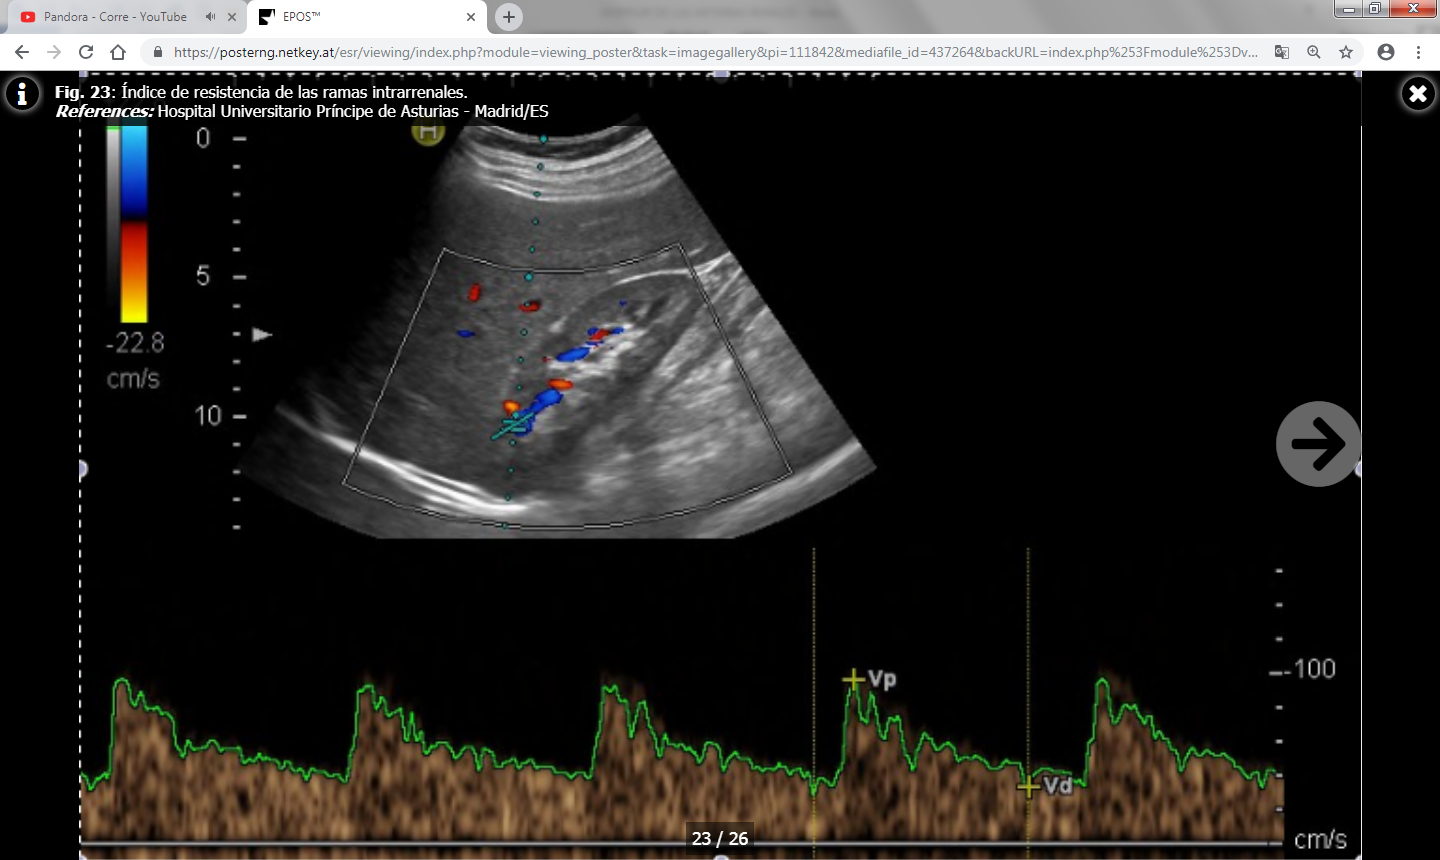

- Índice de resistencia (IR) : Es el resultado del cociente VPS – VTD / VPS (siendo VPS la velocidad picosistólica y VTD la velocidad al final de la diástole). Se debe calcular una media con las distintas medidas obtenidas en cada riñón y valorar si existen diferencias entre un riñón y el contralateral. Lo normal es que el índice de resistencia esté entre 0.6-0.7 y que la diferencia entre ambos riñones sea menor del 5% (ó 0.05). Un aumento de la velocidad telediastólica mayor de 150 cm/s en un paciente con IR intrarrenal menor de 0.7 es altamente sospechoso de estenosis mayor del 80%.

El IR no solamente permite detectar la presencia de estenosis significativas, sino que además predice el pronóstico y la respuesta al tratamiento de revascularización: En un estudio se publicó que en pacientes con IR mayores de 0.8 había escasa respuesta al tratamiento de revascularización ya que la enfermedad renal estaba establecida y era irreversible. No obstante, estos datos han sido ampliamente discutidos en la literatura y no existe acuerdo a día de hoy. - Tiempo de aceleración (TA) e índice de aceleración (IA) : Son parámetros más operador dependientes y por ello menos fiables que el IR. Los valores normales son menores de 0.07-0.08 ms y menores de 3 m/s respectivamente.